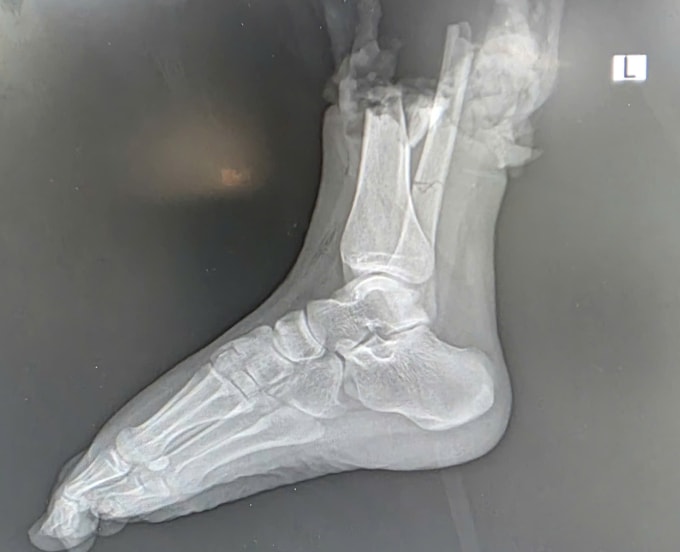

Sau hơn 6 giờ phẫu thuật xuyên đêm, các bác sĩ Bệnh viện Quân đội 108 nối thành công bàn chân phải đứt lìa cho nữ sinh 19 tuổi gặp tai nạn giao thông.

Trước đó, khoảng hai giờ sau cú va chạm với môtô phân khối lớn trên phố Trịnh Văn Bô tối 16/10, nữ sinh quê Bắc Ninh được chuyển đến Bệnh viện 108 trong "thời gian vàng". Các bác sĩ xác định phần cẳng chân phải của bệnh nhân bị đứt lìa, tổn thương phức tạp kèm dập nát phần mềm.

Ngay lập tức, một kíp trực được huy động để phẫu thuật cấp cứu. Các bác sĩ cắt lọc phần dập nát, xử lý tổn thương trước khi thực hiện vi phẫu nối lại mạch máu, thần kinh, gân cơ và xương.

Bác sĩ Nguyễn Điện Thành Hiệp, khoa Phẫu thuật chi trên và Vi phẫu thuật, đánh giá đây là một ca khó vì bệnh nhân còn trẻ, phần chi thể bị tổn thương phức tạp. Tuy nhiên, nhờ được sơ cứu và bảo quản bộ phận đứt rời đúng cách tại tuyến trước, cùng sự phối hợp nhịp nhàng của đội ngũ phẫu thuật, ca mổ thành công.